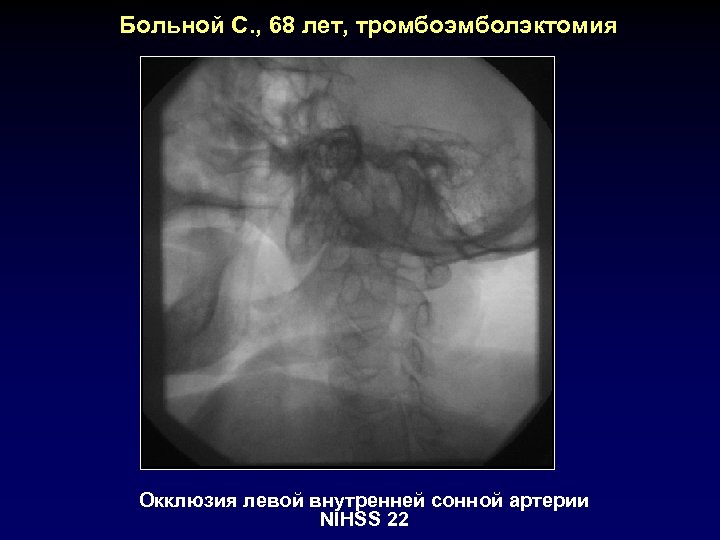

Больной С. , 68 лет, тромбоэмболэктомия Окклюзия левой внутренней сонной артерии NIHSS 22